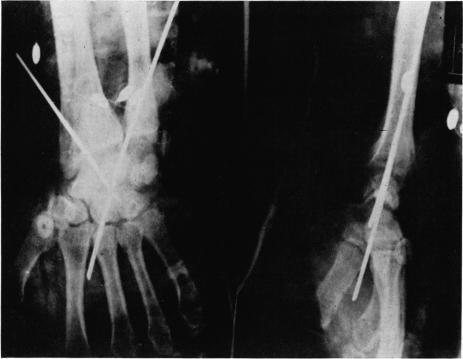

Factors necessary for successful replantation of upper extremities.

Ann Surg. 1967 Feb;165(2):225-38. doi: 10.1097/00000658-196702000-00009.